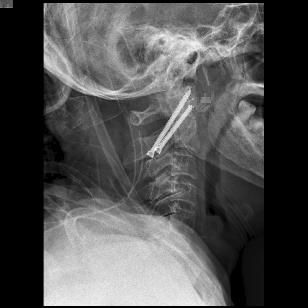

枢椎齿状突骨折后路Margerl手术